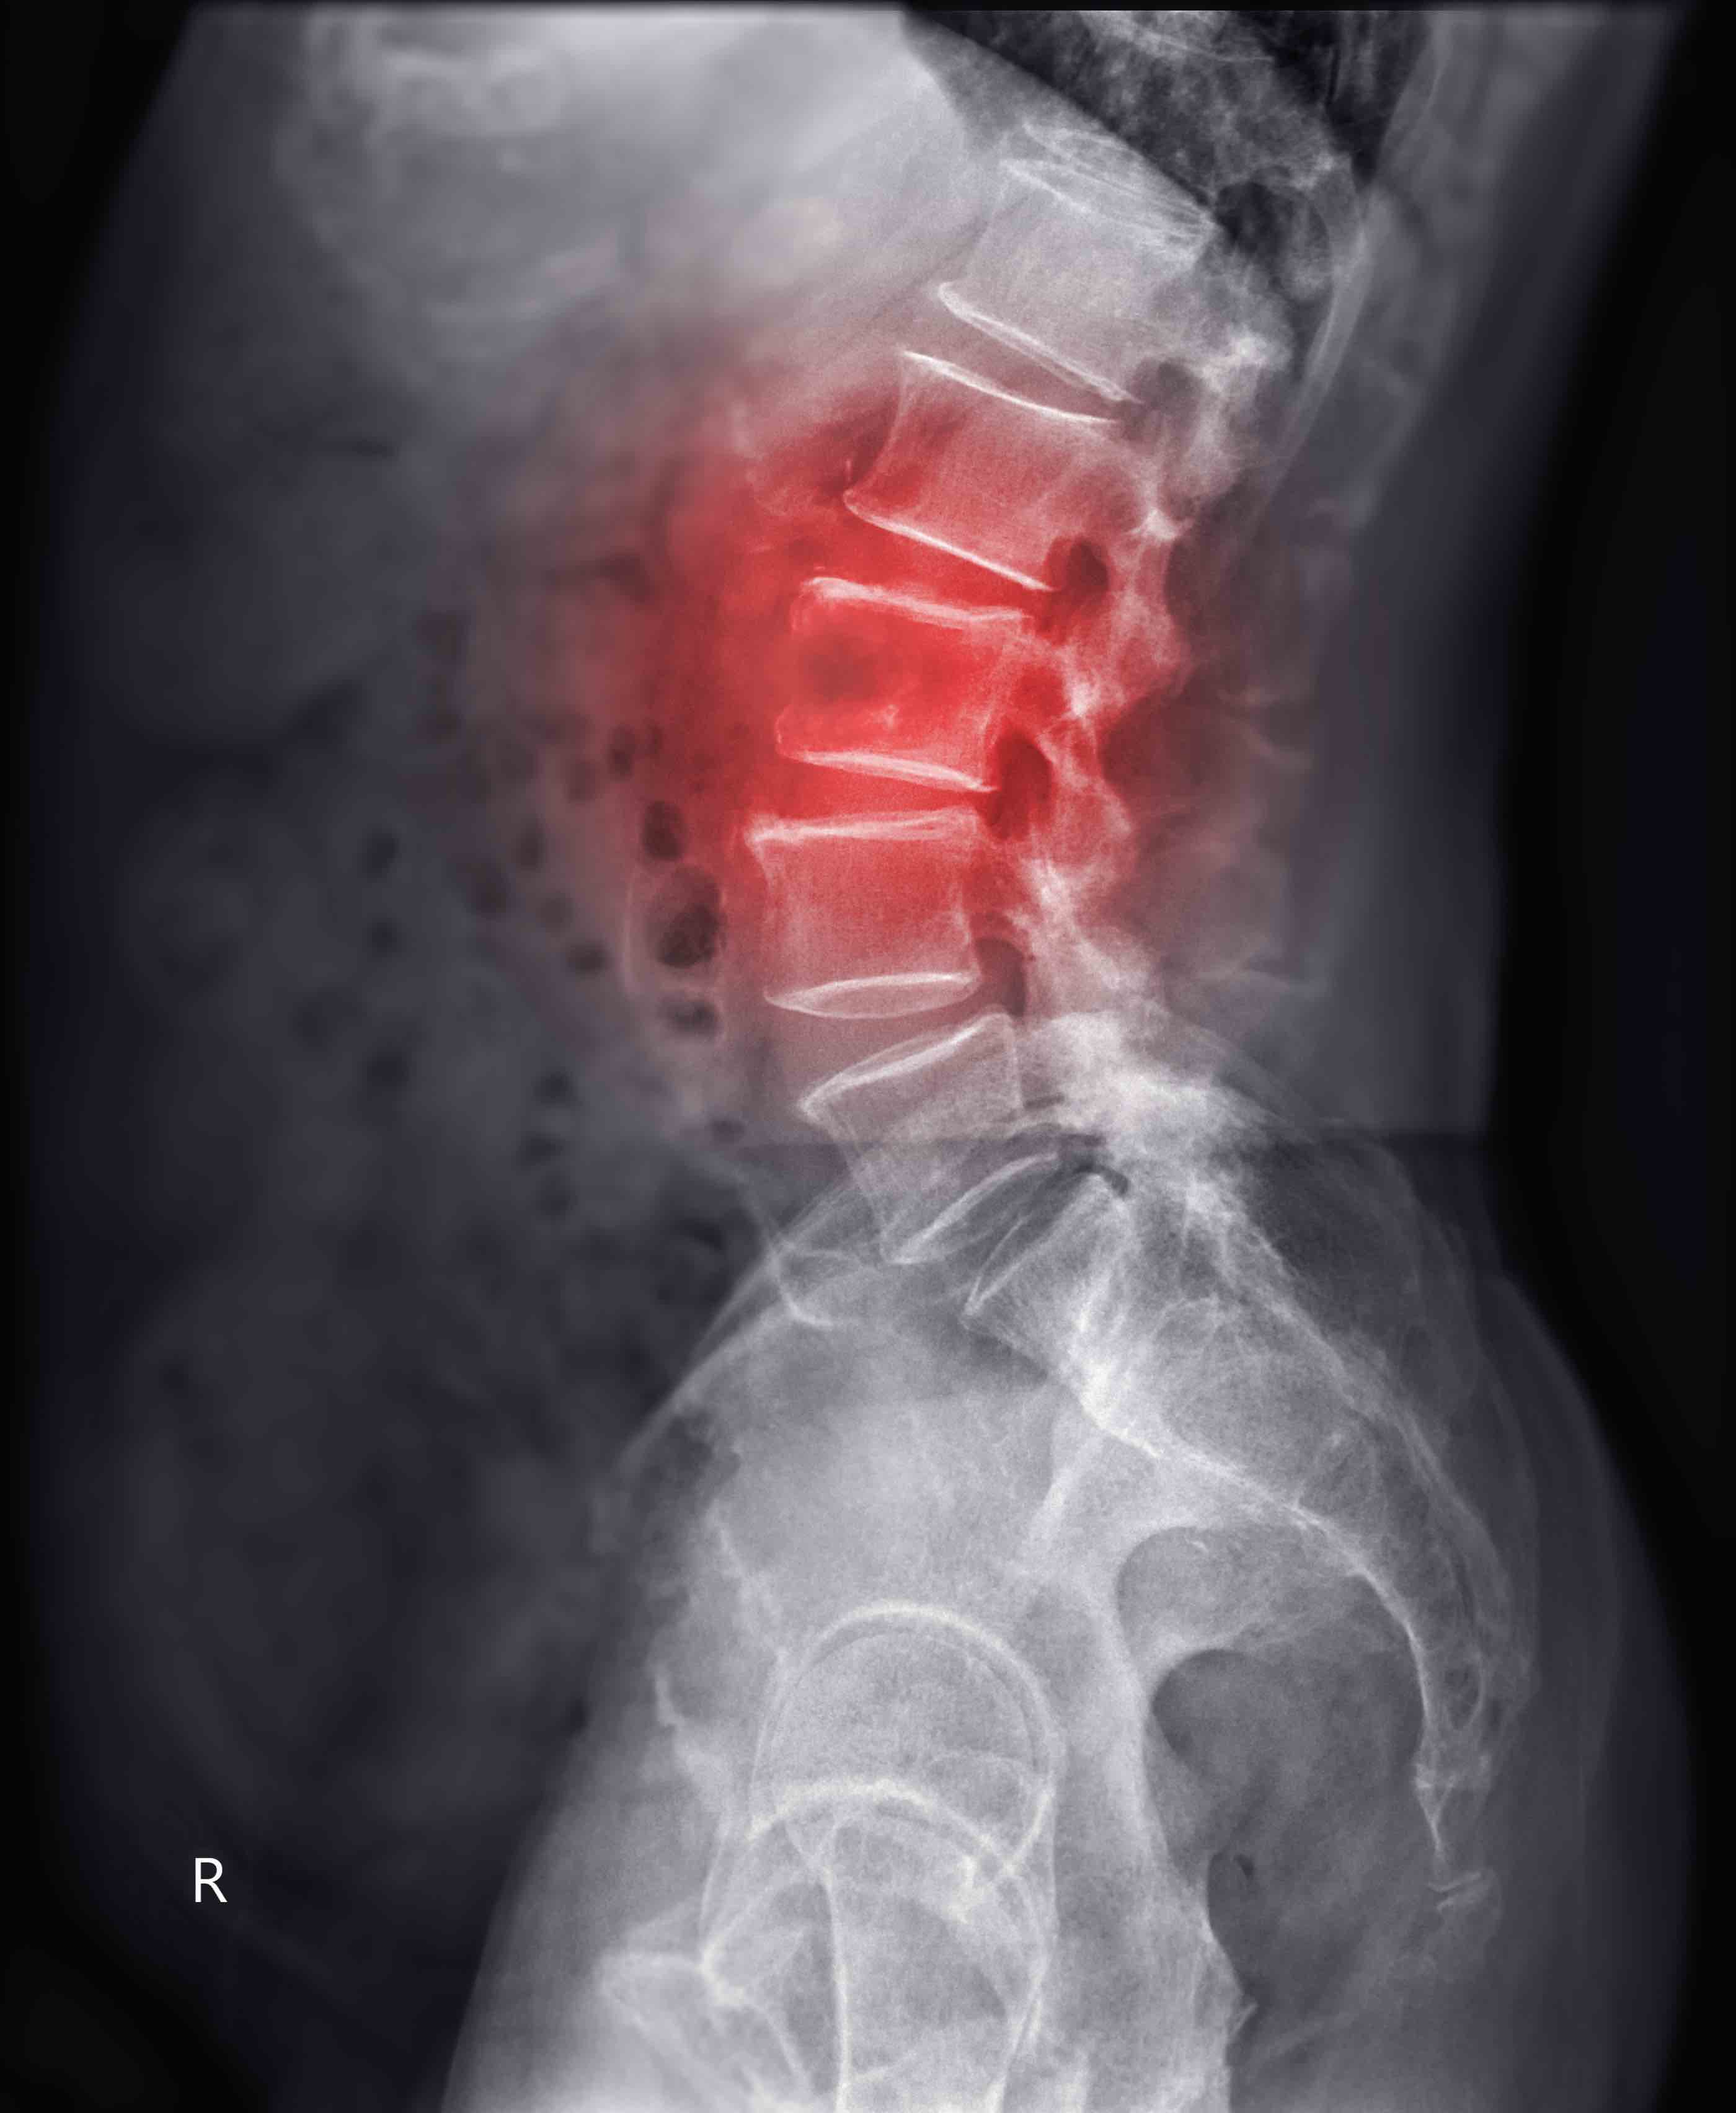

À retenir : Les lésions dégénératives spinales (LD) sont fréquentes dans la spondylarthrite axiale (SpA). Une étude montre qu’à l’inclusion, 53 % des patients présentaient ≥ 1 LD à la radiographie et 94 % à l’IRM. Cette proportion augmentait à 71 % et 97 % respectivement après 10 ans. La progression annuelle était modeste, principalement pour les ostéophytes (2,34 %) et la perte de hauteur discale (1,37 %) sur les radiographies.

- La prévalence des lésions dégénératives a augmenté sur 10 ans, avec une progression annuelle significative pour les ostéophytes (odds ratio 2,34 [1,92-2,75], la perte de hauteur discale (OR 1,37 [0,95-1,80]) et l'arthrose facettaire (OR 1,30 [0,90-1,69]).

- Sur l'IRM, la progression annuelle était notable pour la hernie discale (OR 1,19 [0,74-1,64]), les lésions Modic type I (OR 1,01 [0,69-1,33]) et type II (OR 0,94 [0,66-1,22]).

- Une augmentation significative du nombre total de lésions dégénératives a été observée sur les radiographies et à l'IRM.